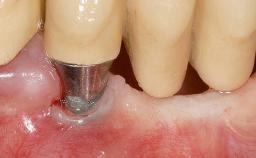

Early Implant Placement, Contour Augmentation, and Autologous Connective-Tissue Graft Using a Tunneling Technique to Replace an Upper Incisor with Generalized Gingival Recession

| # of Implants | 1 |

| Type of Implants | Reduced-Diameter|Two-Piece |